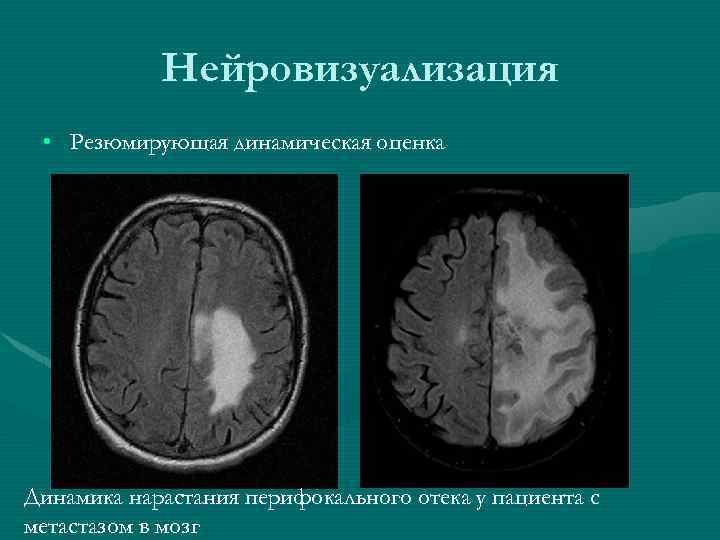

Нейровизуализация • Резюмирующая динамическая оценка Динамика нарастания перифокального отека у пациента с метастазом в мозг